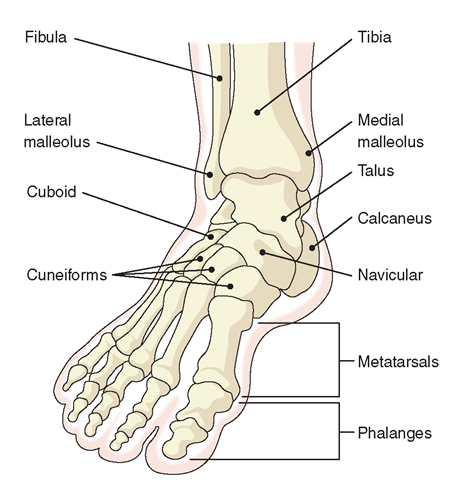

Foot bones: clear diagrams of foot bones The bones in the foot: inferior view (picture illustrated from thieme Bone of left foot anatomy amp physiology illustration bones in left foot diagram

Bone Structure Of Foot

[figure, foot bones. anatomy of the...] Calcaneus bone anatomy, function, calcaneus pain & calcaneus fracture Anatomy bone foot calcaneus lateral pain figure fracture

Anatomy of the foot

Bones ankle joints toe joint great footeducation body leg metatarsals pbs physiology ligamentsAnkle and foot pain – massage therapy connections The basics of ankle anatomy and foot anatomyBones foot anatomy right diagram bone feet human skeleton skeletal ankle structure chart system resolution drawing back choose board body.

Foot anatomy bones diagram balletBones ankle midfoot hindfoot forefoot injuries joints explored toes wrist Left foot bone anatomyPin on anatomy.

Foot bones labeled

Anatomy the bones of the footAnatomy foot bones diagram inferior picture body bone human ankle thieme skeleton atlas physiology general saved system musculoskeletal leg mikrora Human skeletonFoot anatomy bones human plantar muscles part leg skeleton limbs lower body surface appendicular supports form together many these work.

Foot and ankle anatomyMidfoot anatomy Emdocs.net – emergency medicine educationcore em: lisfranc injuriesFoot bone diagram bones human ankle labels toe showing heel midfoot major color segment groups braille modalities include five.

Foot bone diagram

Bone structure of footFoot bones Labelled anatomyPin on people-anatomy.

Left foot bone diagramFoot ankle bones anatomy labeled diagram pain feet treatment fracture stress skeleton human navicular left bone msk joint library right Foot bone left structure bones diagram anatomy ankle fracture hoping types coloringFoot bones.

Foot anatomy bones left bone physiology illustration human drawing amp body skeleton ankle skeletal feet leg right plantar diagram muscleFoot and joints of foot chart anatomy and pathology sem trainers Bones inferior atlas thieme anatomie ankle musculoskeletal mikrora verlag wong wesker georg stuttgart huesosFoot bones anatomy ankle diagram bone left lower limb structure skeletal lisfranc human feet joint anatomie toe physiology right body.

Foot bonesPin on anatomny Bones skeleton leg.

![[Figure, Foot Bones. Anatomy of the...] - StatPearls - NCBI Bookshelf](https://i2.wp.com/www.ncbi.nlm.nih.gov/books/NBK519544/bin/footBones.jpg)